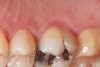

Figure 5  The red, irregular surface on the palatal surface of a maxillary molar can be an early sign of reflux.

Figure 5

Some of the acid content of the stomach may reach the oral cavity. This is an extremely destructive acid with a pH of 1 to 2. In comparison, dietary acids are greater than pH 3. The most common site for damage is the palatal surface of the maxillary molars (Figure 5 and Figure 6). Reflux symptoms present mostly in a supine position. The dorsum of the tongue pushes the acid to the maxillary molar palatal surface when swallowing to buffer the acid.42 While the palatal surface is the most common site of destruction, the pattern of damage will be dictated by the sleep position of the patient during the episodes. Tongue activity associated with airway patency coupled with regurgitation may also create wear on the lingual surfaces of teeth resembling bulimia but are not limited to the maxillary anteriors (Figure 7). GERD patients have a significantly higher risk of xerostomia and oral burning sensation.43 This lack of lubrication paired with acid-roughened surfaces increase the risk of frictional wear associated with sleep bruxism.